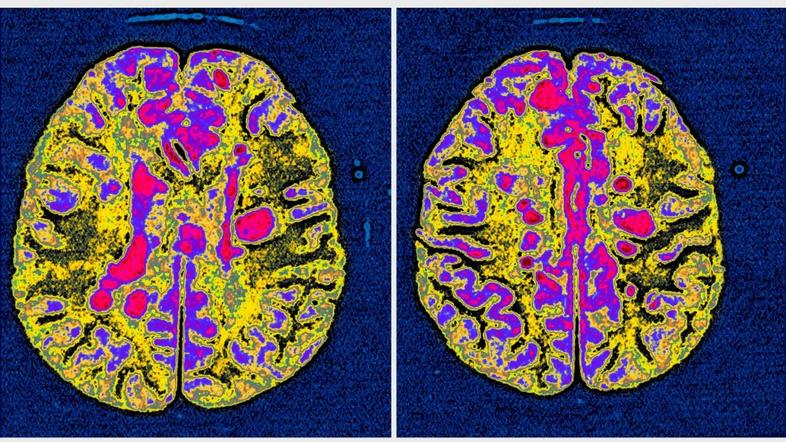

Multipla skleroza: Tako sonce vpliva na razvoj te neozdravljive bolezni

Multipla skleroza je kronična avtoimuna vnetna bolezen, ki prizadene osrednje živčevje, kar povzroča šibkost in oslabi motorične sposobnosti. Bolezen povzroči propadaje ovojnice živčnih vlaken zaradi poškodb in izgube mielina.